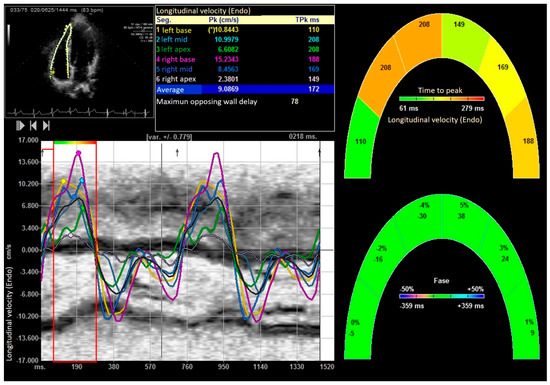

| Peak systolic longitudinal velocity (cm/s) | 4.98 ± 0.12 | 4.01 ± 10.21 | 9.48 ± 3.25 | 0.001 |

| peak E longitudinal velocity (cm/s) | −5.6 ± 1.35 | −4.2 ± 0.87 | −7.38 ± 3.15 | 0.0001 |

| peak A longitudinal velocity (cm/s) | −4.01 ± 0.74 | −3.75 ± 0.98 | −5.14 ± 1.48 | 0.0001 |

| Right ventricular Longitudinal Strain delay (ms) | 144.88 ± 22.52 | 168.92± 29.35 | 98.27 ± 12.11 | 0.0001 |

| Right ventricular longitudinal global right Strain rate (1/s) | −1.79 ± 0.078 | −1.48 ± 0.33 | −2.88 ± 0.25 | 0.0001 |

| Right ventricular Longitudinal systolic displacement (mm) | 6.12 ± 1.18 | 5.09 ± 3.22 | 10.88 ± 1.25 | 0.0001 |